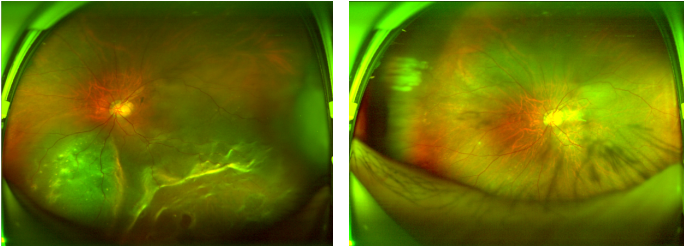

(图二:欧堡眼底照相下张先生左眼孔源性视网膜脱离手术前后对比如图所示)

抱着一线希望,张先生来到岳阳爱尔眼科医院眼底病门诊就诊。眼底病科副主任医师汪洁为其进行了详细检查,发现其左眼下方视网膜呈青灰色隆起僵硬,已累及黄斑区,网膜下可见大量白点,视网膜下方还有数个类圆形视网膜裂孔,其余视网膜平伏,黄斑区反光欠清,明确诊断为“左眼孔源性视网膜脱离”,并立即将其收入院准备手术。

据汪洁主任介绍,视网膜脱离是指视网膜神经上皮和色素上皮的分离,多由视网膜裂孔、机械性牵拉等因素引发,50岁以上人群为高发群体,典型症状包括眼前闪光感、黑影飘动、视力减退、视野缺损等,若不及时治疗,脱离时间越长,永久性视力丧失的风险就越大,尤其是累及黄斑区时,视力恢复难度会显著增加。张先生所患的视网膜脱离已累及黄斑区,需及时通过手术封闭裂孔、促进视网膜复位。

随后,医护团队为张先生制定了个性化手术方案,成功实施了左眼后入路玻璃体切割术、左眼玻璃体硅油置入术及左眼视网膜脱离激光治疗术。其中,玻璃体切割术作为治疗眼底病的“神兵利器”,可切除混浊玻璃体、解除视网膜牵拉,配合硅油置入和激光治疗,能有效帮助视网膜复位,最大程度挽救视功能。术后,在医护团队的精心护理和悉心指导下,张先生恢复状况良好,左眼视力逐步提升,已然摆脱了视力模糊的困扰。